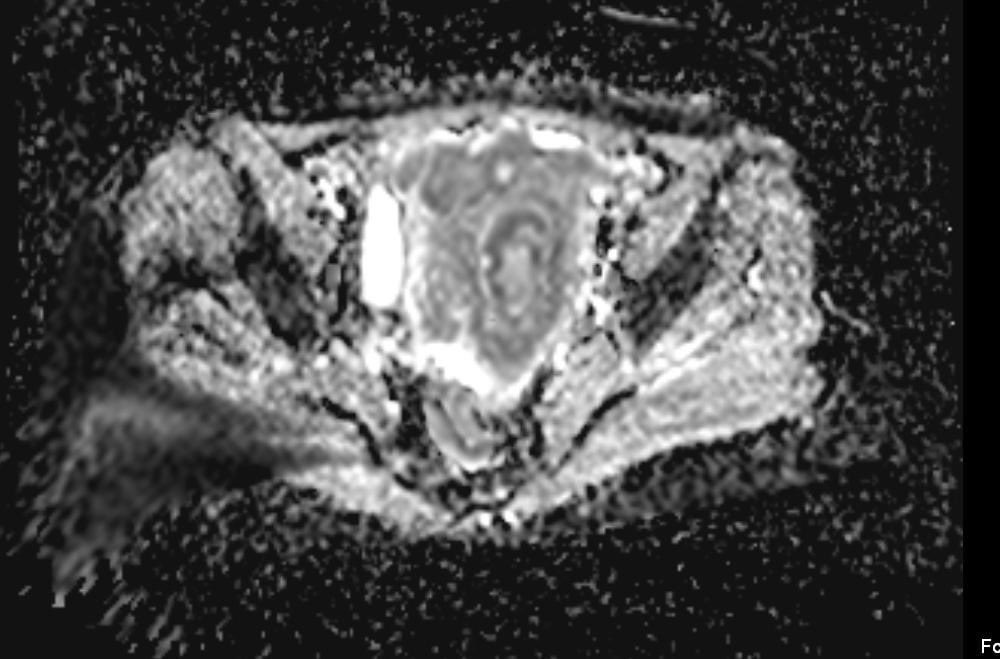

- 58-year-old female with vaginal bleeding for the past 2 months - findings and diagnosis ? #MEDHM @IhabFathiSulima #MedEd #MedX

hemo_shk's tweet image. - 58-year-old female with vaginal bleeding for the past 2 months

- findings and diagnosis ?

58-year-old female with active vaginal bleeding #Findings: •There is thickening of the endometrium measuring 14mm in thickness with internal intermediate signal intensity seen. •The lesion is seen extending into the myometrium with invasion of the serosa layers. •The lesion

#Findings:

•There is thickening of the endometrium measuring 14mm in thickness with internal intermediate signal intensity seen.

•The lesion is seen extending into the myometrium with invasion of the serosa layers.

•The lesion